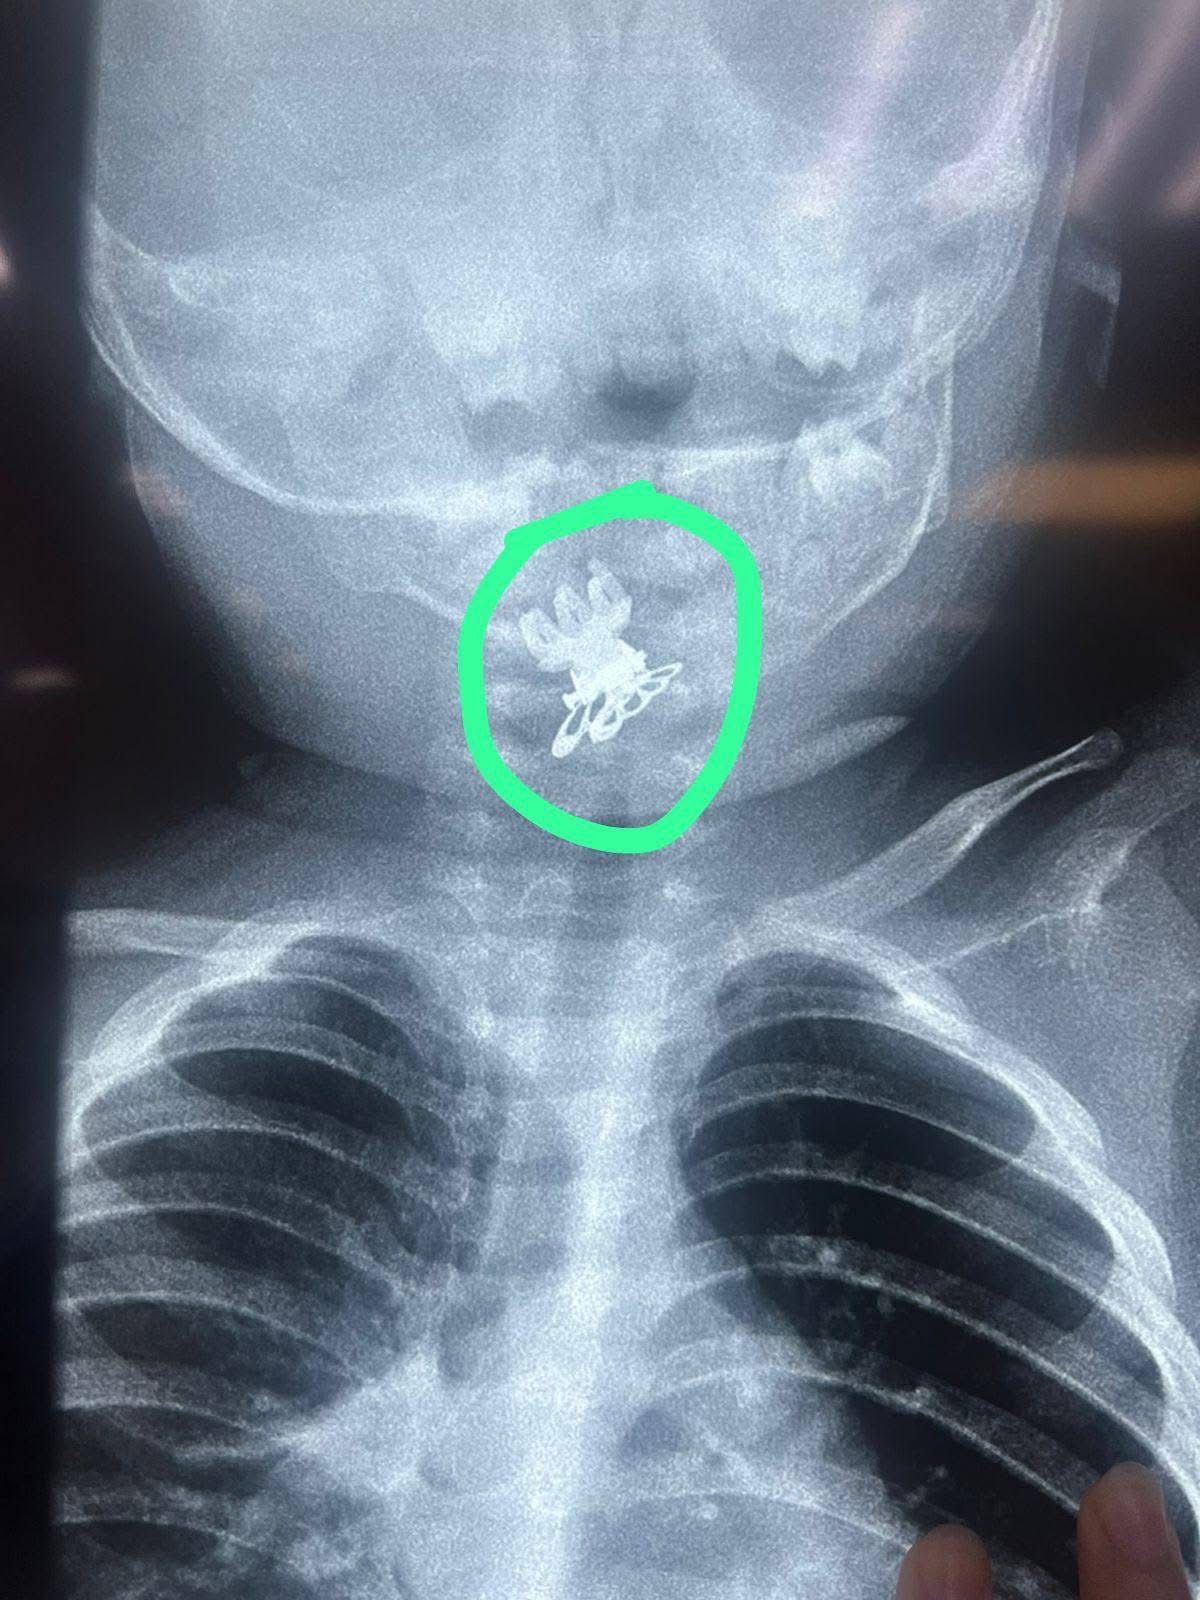

تمكن فريق طبي بمدينة الصدر الطبية في النجف الأشرف من إنقاذ حياة طفلة تبلغ من العمر سنة ونصف، بعد تعرضها لحالة اختناق حاد نتيجة ابتلاع مشبك شعر (قراصة) استقرت في مدخل المجرى التنفسي

وبينت صحة النجف ان طوارئ مستشفى الصدر استقبلت الطفلة تعاني من ضيق تنفس وسعال شديد، وبعد اجراء الفحوصات الفورية وجود الأطباء جسم غريب وتم ادخالها الى غرفة العمليات وإزالة بمنظار خاص دون مضاعفات.